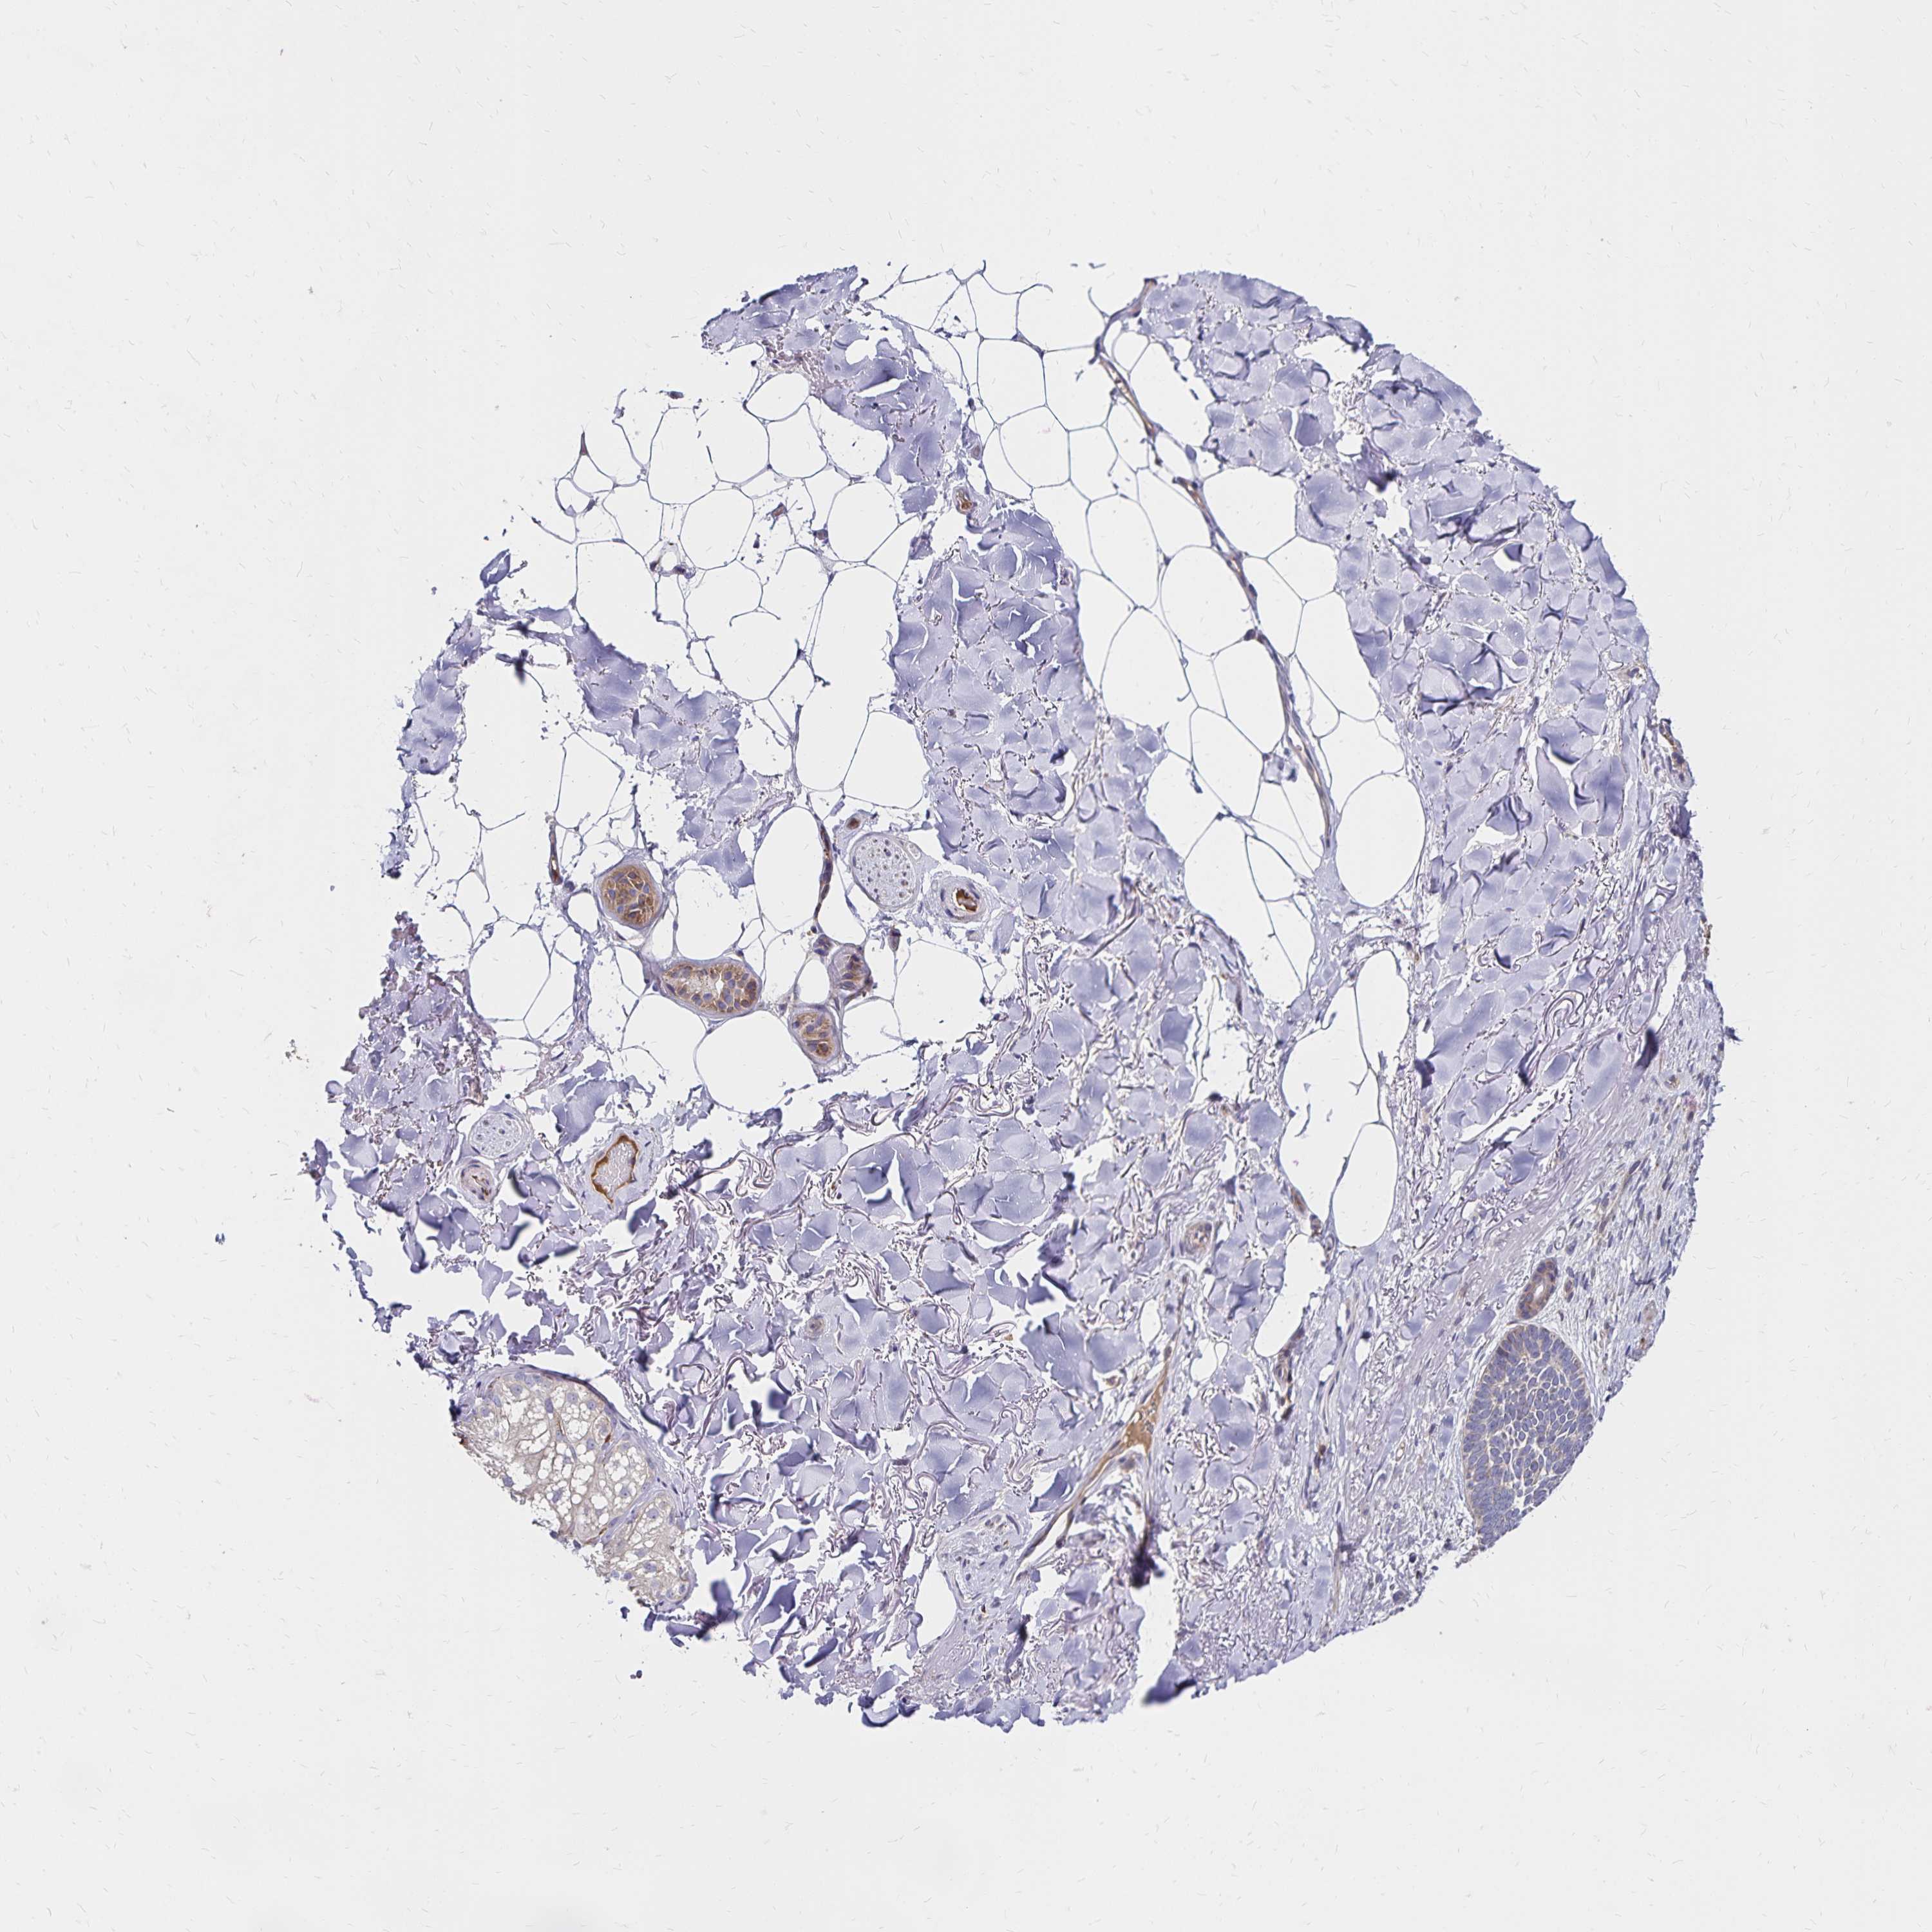

CANCER SKIN CANCER Show tissue menu

Basal cell and squamous cell cancer

SKIN CANCER - Protein expressioni

A mouse-over function shows sample information and annotation data. Click on an image to view it in a full screen mode. Samples can be filtered based on level of antibody staining by selecting one or several of the following categories: high, medium, low and not detected. The assay and annotation is described here.

Each image is clickable and will lead to virtual microscopy that enables deeper exploration of all samples and also displays staining intensity scores, fraction scores and subcellular localization as well as patient and tissue information for each sample.

Antibody HPA064055

Staining

High

Medium

Low

Not detected

Intensity

Strong

Moderate

Weak

Negative

Quantity

>75%

75%-25%

<25%

None

Location

Nuclear

Cytoplasmic/membranous

Cytoplasmic/membranous,nuclear

Basal cell carcinoma

Squamous cell carcinoma, NOS